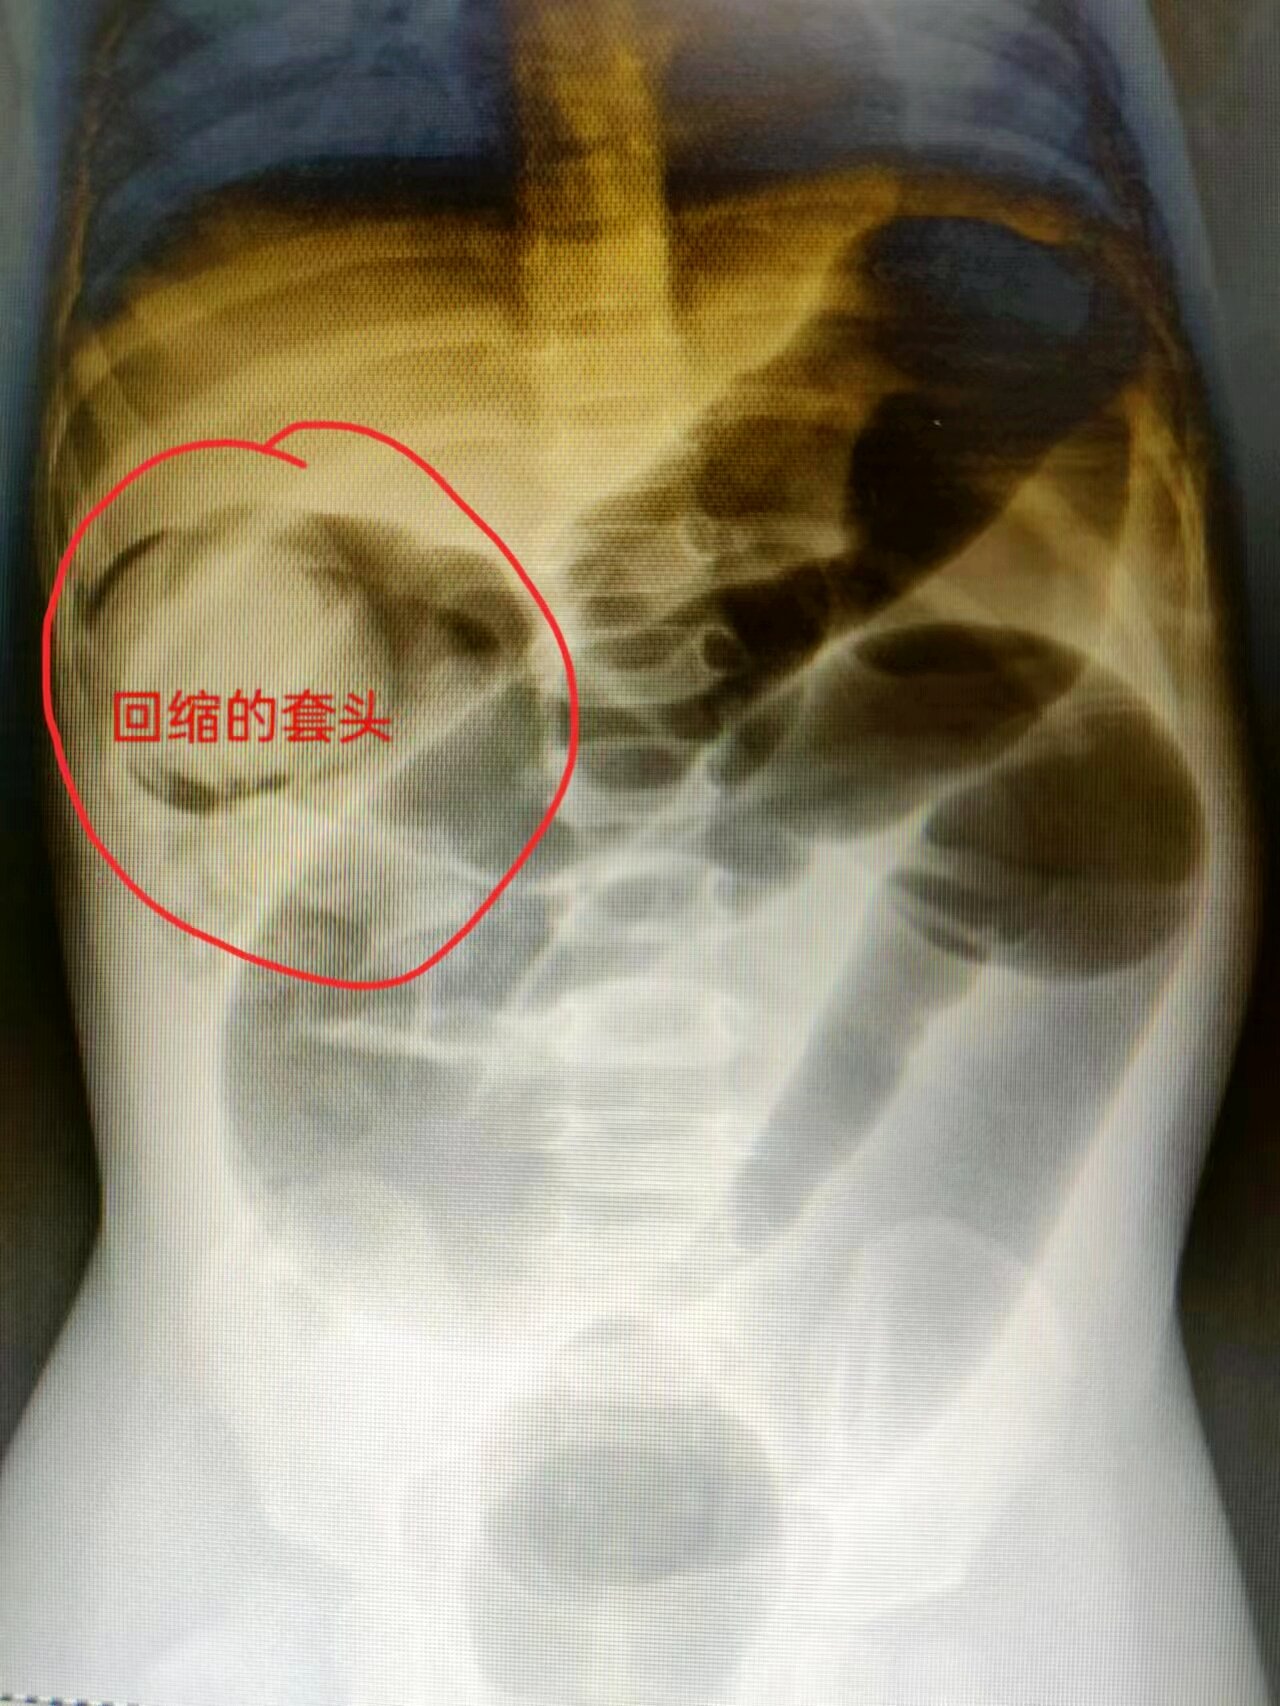

入院后,兒童重癥醫(yī)學(xué)科主治醫(yī)師張茜第一時間進(jìn)行擴(kuò)容,補液糾正休克、電解質(zhì)紊亂等以確?;純喊踩写才圆食瑱z查明確診斷為腸套疊、不排除腹內(nèi)疝,同時聯(lián)系小兒外科主任王松陽、主治醫(yī)師王艷平進(jìn)行會診,會診查體摸到患兒腹部包塊,行手法復(fù)位可由7cm大小縮小至3cm,進(jìn)一步復(fù)位困難。王松陽主任考慮患兒病情危重,且年齡小,建議盡量保守治療解決患兒腸套疊癥狀,并陪同患兒及家屬至放射科行空氣灌腸,預(yù)防空氣灌腸途中突發(fā)腸破裂、呼吸心跳驟停等意外。經(jīng)多次嘗試,腸套疊套頭可縮小但不能完全復(fù)位,且復(fù)位過程中患兒多次排血便。